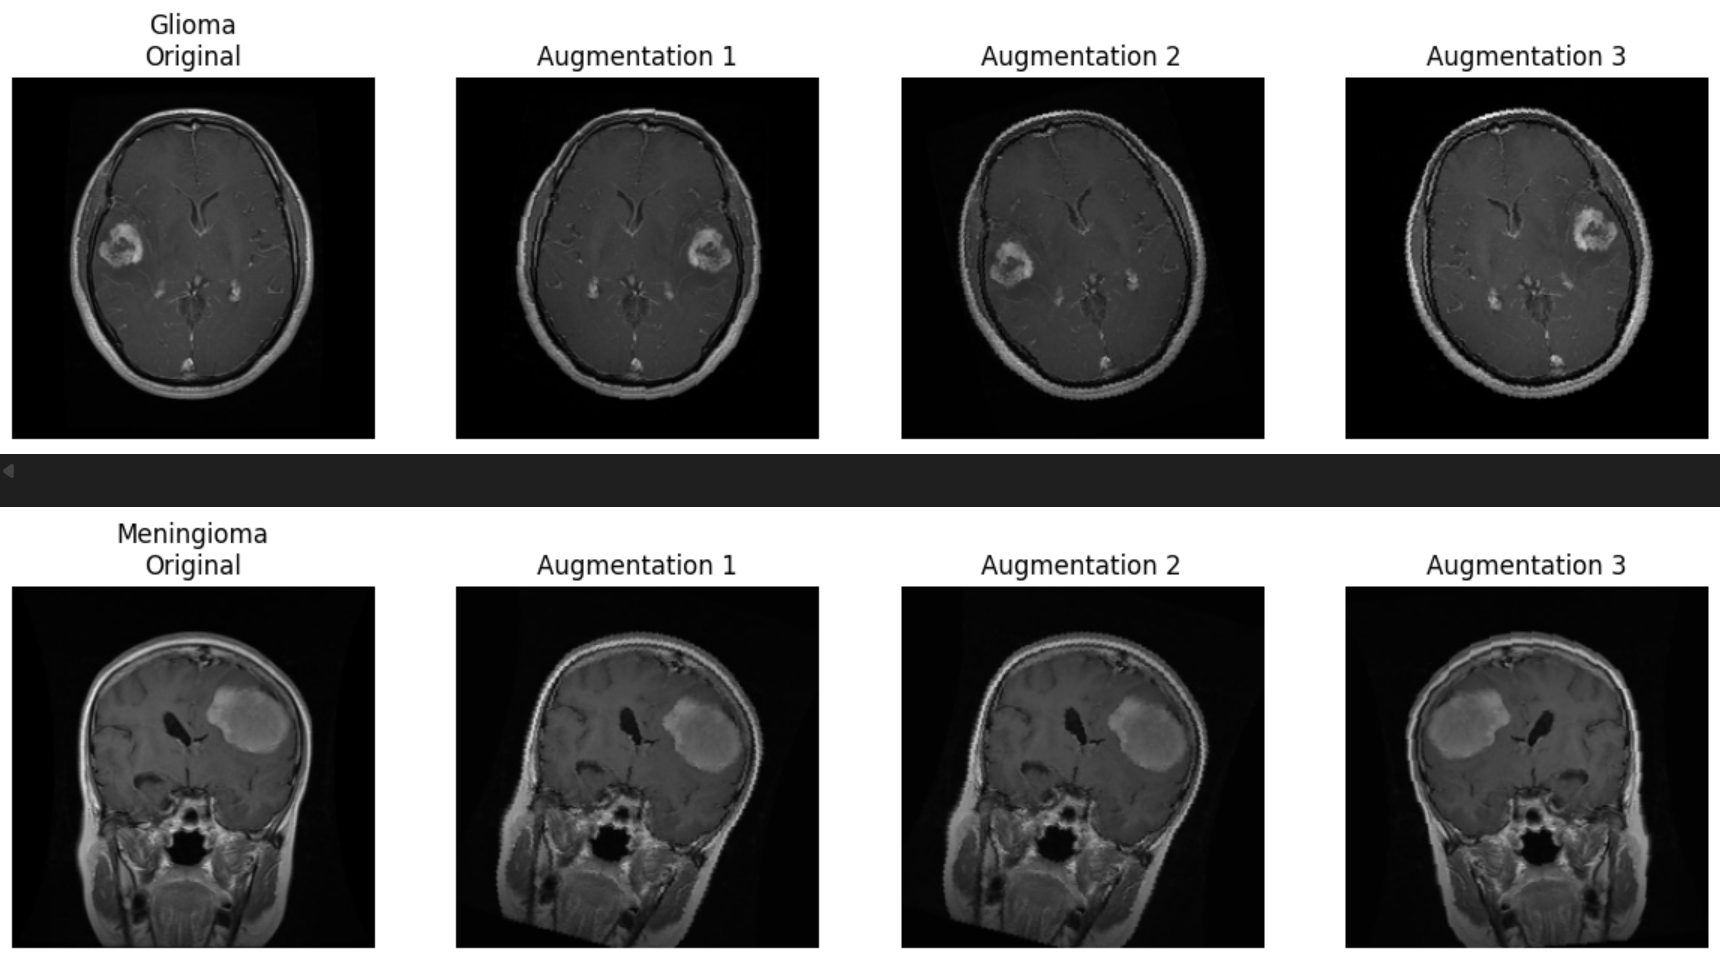

We also conducted a systematic review of the data augmentation strategy to ensure compatibility with medical imaging features (Figure 3). As demonstrated in the figure below, each original image underwent a series of transformations including random horizontal flips, affine transformations (rotation, shear), and brightness shifts. These augmentations were chosen to simulate common variability in scan acquisition while enhancing model robustness. To verify that diagnostic features—such as lesion shape, tumor boundary, and intensity profile—were not distorted, qualitative evaluations were performed across all tumor classes. No visible degradation or artificial signal was introduced by the applied transformations, and model performance remained stable across validation folds.

Figure 3: Example of augmentation strategies (flip, brightness, rotation) applied to glioma and meningioma samples.

MRI Augmentation Samples

Augmentation can introduce bias if transformations inadvertently alter class-specific features or introduce artificial regularities not present in real data. In medical imaging, particular caution must be exercised with spatial and intensity manipulations to avoid creating anatomically implausible artifacts. Our validation confirmed that the augmentations preserved key tumor features, and thus contributed positively to generalization while maintaining clinical interpretability.